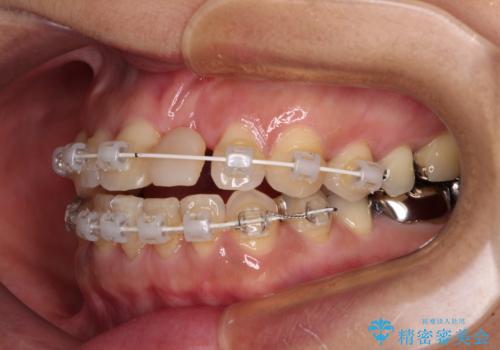

中途半端な矯正治療と前歯の欠損 再矯正とオールセラミッククラウンによる補綴治療

- 矯正治療を行ったものの、隙間やデコボコが多く、欠損している前歯も気になるとのことで来院された患者様です。

当初はセラミック治療だけを希望されていましたが、上下前歯のデコボコが顕著であったため、セラミッククラウンにて治療する前に再度矯正治療を行った方が仕上がりがきれいになると説明し、再矯正を行うこととしました。

矯正治療により前歯横幅のバランスを整えた後に、上顎前歯をオールセラミックブリッジにて補綴治療を行うこととしました。

舌突出癖により、上下前歯が突出して離開してしまったため、舌のトレーニングを徹底的に行いました。